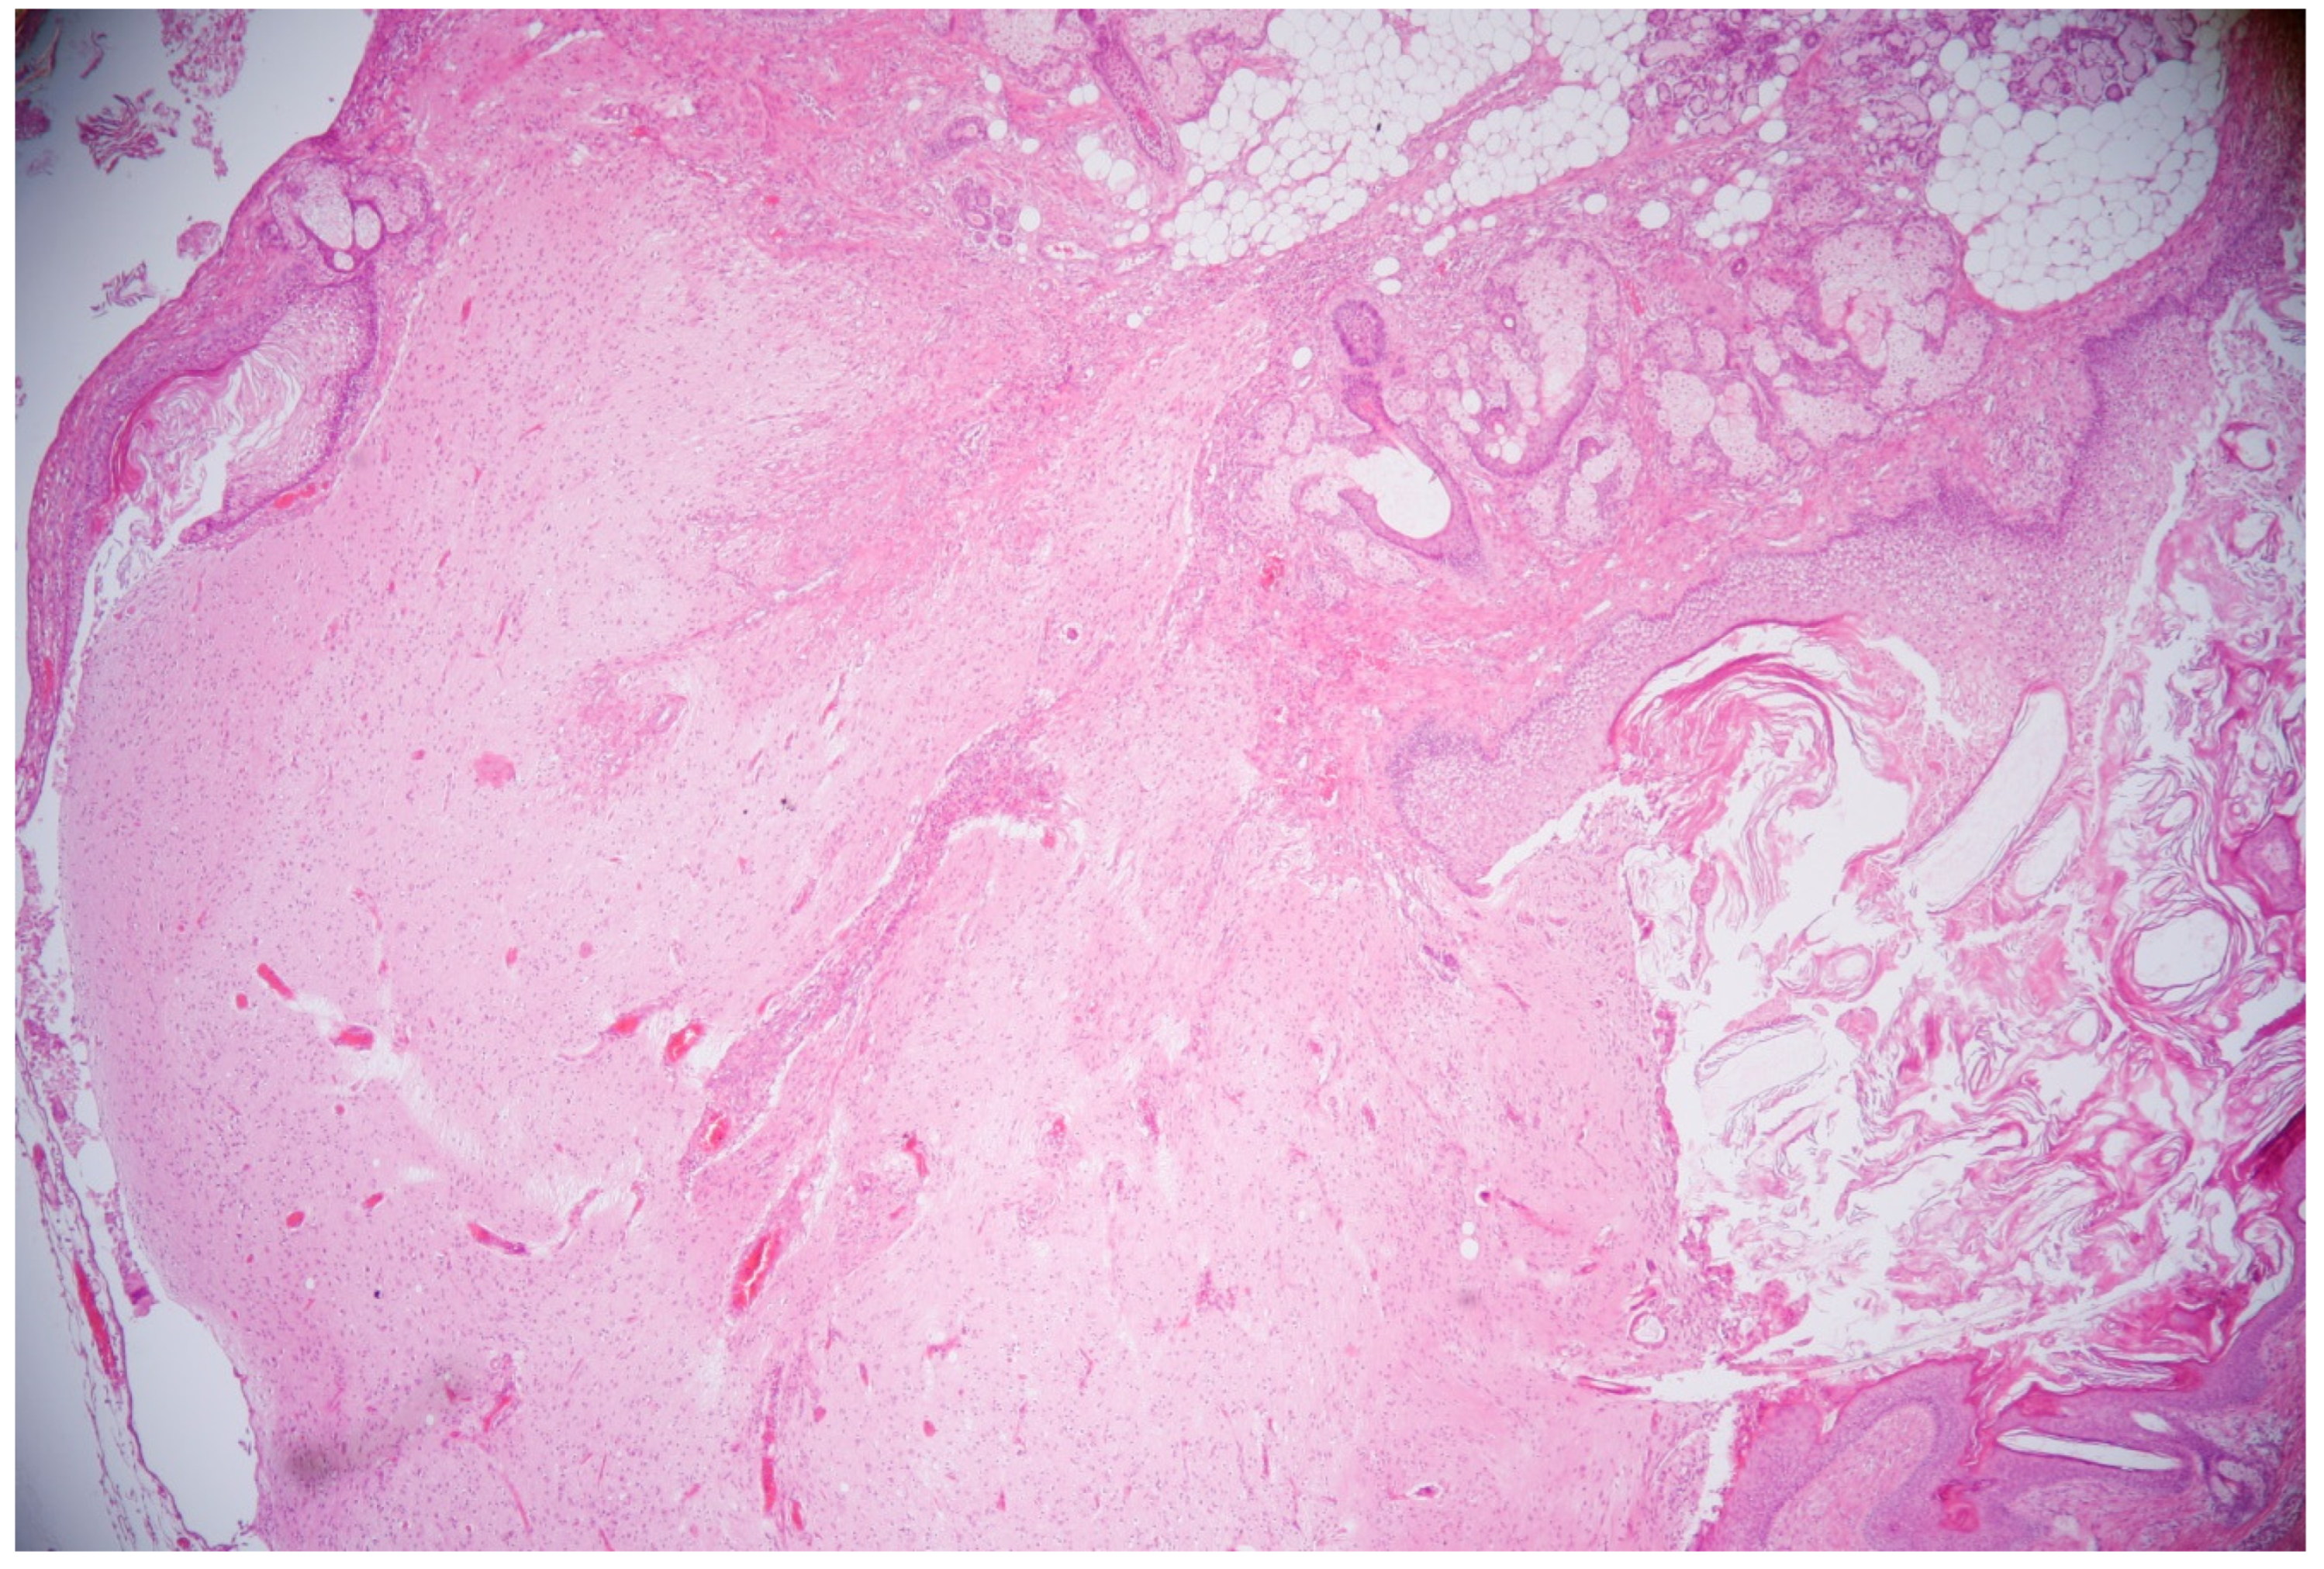

While there was no response to the first-line immunotherapy, second-line immunotherapy with rituximab (375 mg/m2/every two weeks for two cycles) was initiated, and this immunotherapy included the use of cyclophosphamide (after 2 months, a monthly dose of 750 mg/m2 was used). The patient also underwent a laparoscopic right-ovary cystectomy. After tumor removal, the histological findings revealed a mature ovarian teratoma. Hematoxylin–eosin (HE) staining revealed a characteristic spectrum of elements, including stratified squamous epithelium and cutaneous adnexal structures (sweat glands and pilosebaceous units with hair follicles and sebaceous glands) and fat tissue accompanied by neuroglial cells (Figure 4).

Figure 4. Histological appearance of mature ovarian teratoma composed of different structures—stratified squamous epithelium, cutaneous adnexal structures (sweat glands, pilosebaceous units with hair follicles and sebaceous glands), fat tissue, and neuroglial cells. HE, 40x magnification.